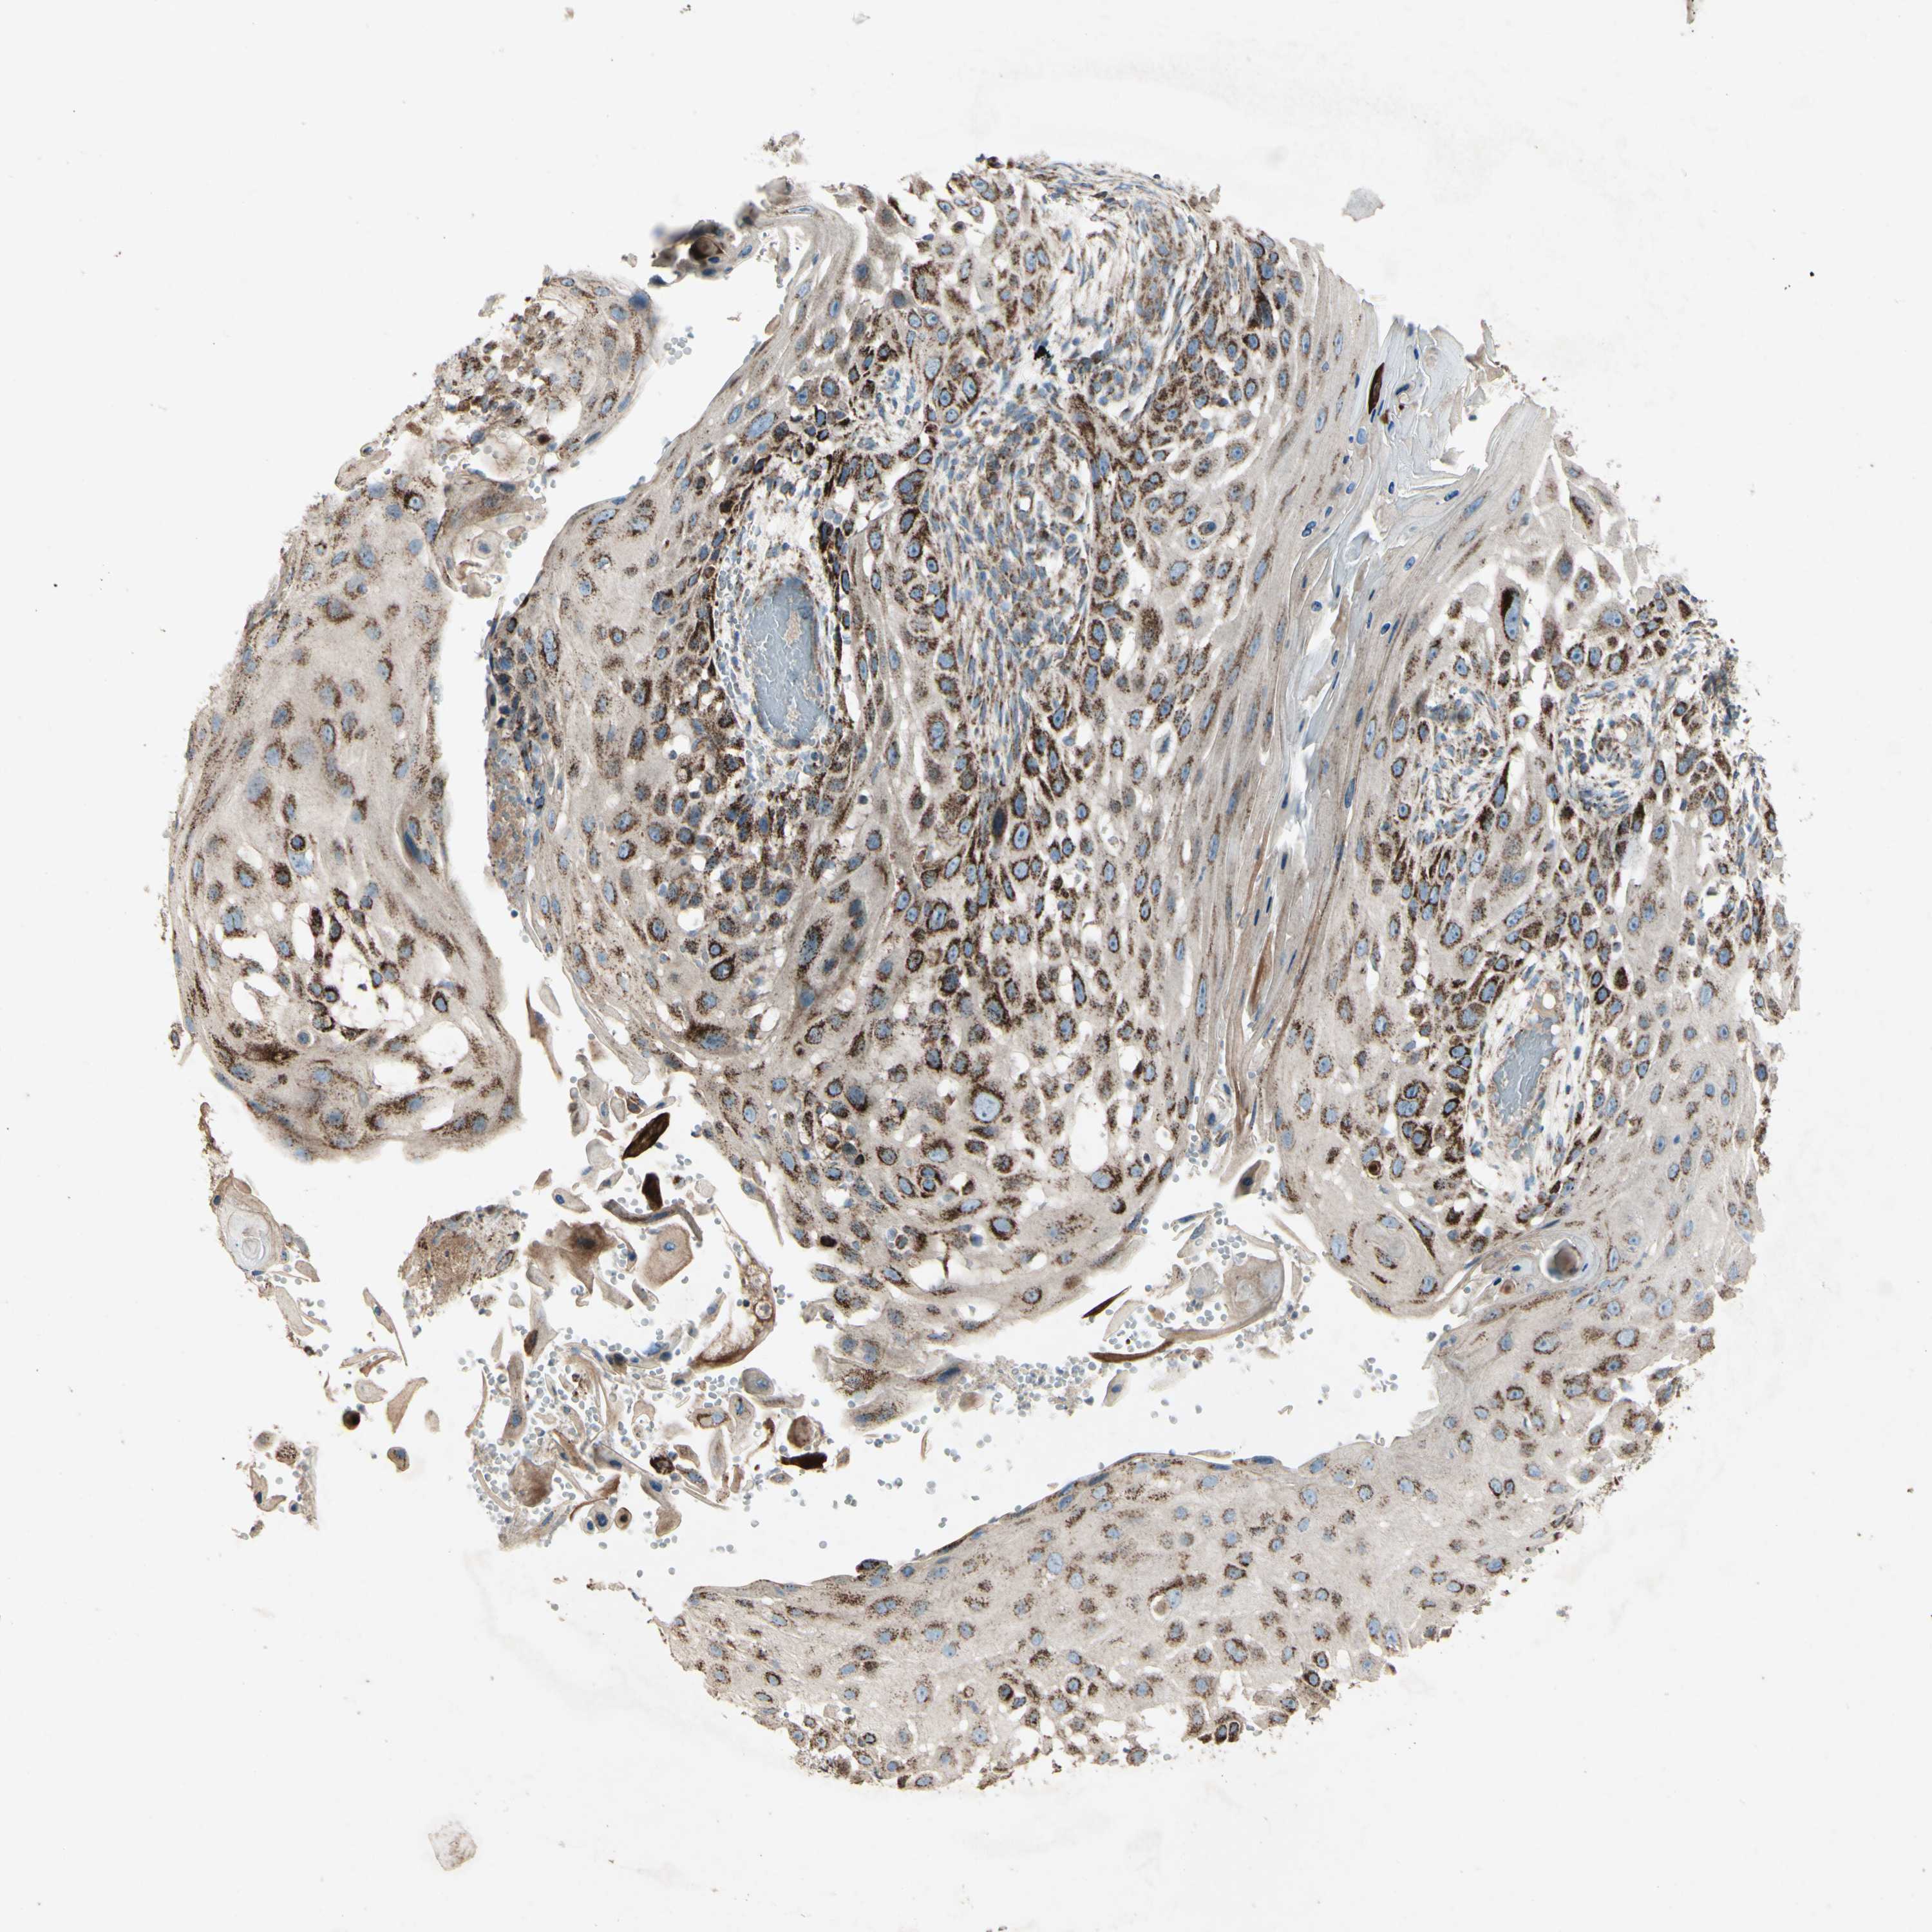

SKIN CANCER - Protein expressioni

A mouse-over function shows sample information and annotation data. Click on an image to view it in a full screen mode. Samples can be filtered based on level of antibody staining by selecting one or several of the following categories: high, medium, low and not detected. The assay and annotation is described here.

Each image is clickable and will lead to virtual microscopy that enables deeper exploration of all samples and also displays staining intensity scores, fraction scores and subcellular localization as well as patient and tissue information for each sample.

Antibody HPA010687

Staining

High

Medium

Low

Not detected

Intensity

Strong

Moderate

Weak

Negative

Quantity

>75%

75%-25%

<25%

None

Location

Nuclear

Cytoplasmic/membranous

Cytoplasmic/membranous,nuclear

Squamous cell carcinoma, NOS

Squamous cell carcinoma, metastatic, NOS

Basal cell carcinoma

Papilloma, NOS